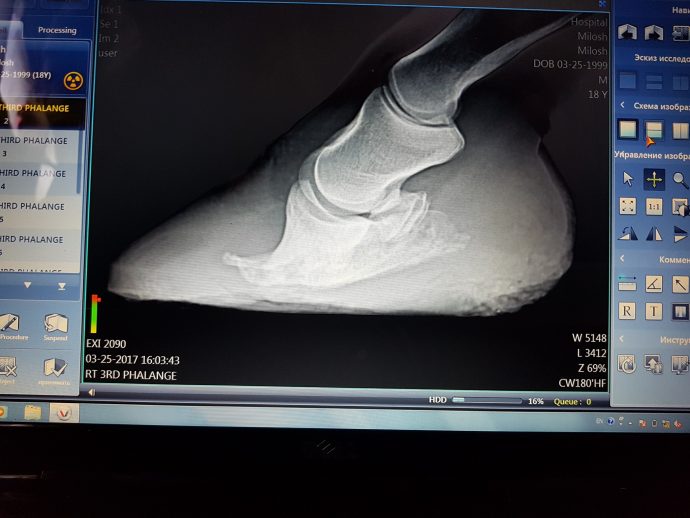

Dieses Pferd leidet an Hufrehe und lebt in Russland. Am 25.3.2017 fand nun in Moskau der erste Schmiedetermin mit Ulrich Gerusel statt. Ein Tierarzt war ebenso vor Ort und röntgen die Hufe, um in Zusammenarbeit mit dem Hufschmied die Bearbeitung zu optimieren.

In regelmäßigen Abständen wird Hufschmied Gerusel nun nach Moskau fliegen, um diesem Pferd und weiteren Pferden zu helfen.